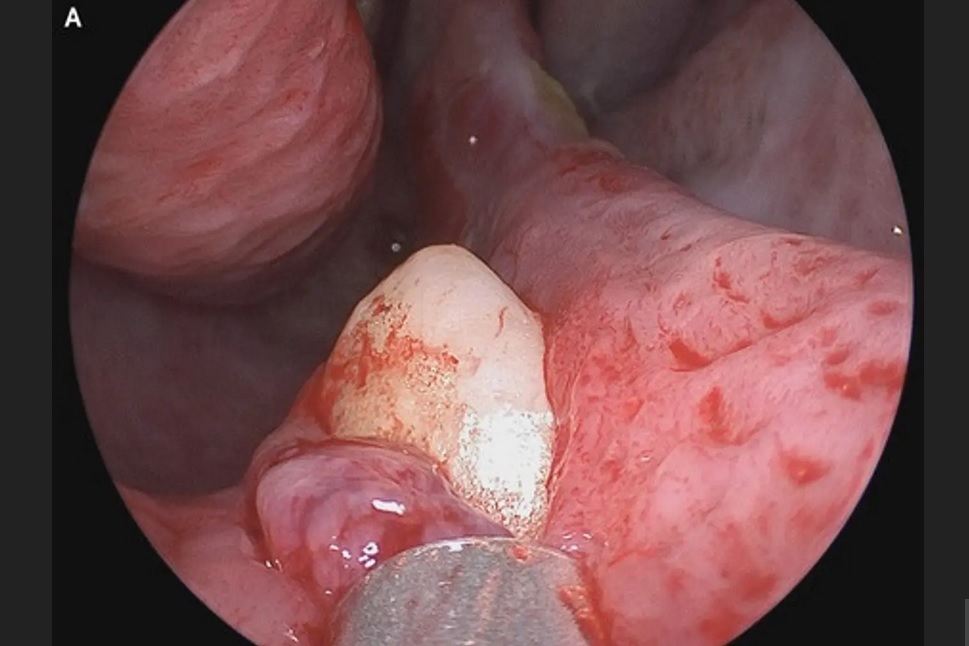

پزشکان در این مطالعه گفتند که معاینه فیزیکی این شخص، یک انحراف در سپتوم را نشان میدهد. انحرافی که دو سوراخ بینی را از هم جدا میکند. این معاینه همچنین سوراخی به طول ۲ سانتی متر در پشت سپتوم و انسدادهای کلسیفیه را نشان داد. پس از بررسیهای بیشتر مشخص شد که یک دندان در داخل بینی این شخص رشد کرده است.

دندان این بیمار که به طول ۱۴ میلی متر بود با عمل جراحی برداشته شد. پزشکان تایید کردند که مشکل تنفسی بیمار پس از معاینه و سه ماه پس از انجام جراحی به طور کامل برطرف شد.